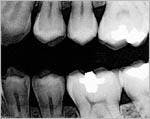

We noticed a vertical line running from the bottom of his amalgam restoration down to the pulp chamber. When we enhanced the image using the Clear-Vu tool in our DEXIS digital radiography system (see Figure 2), the fracture was clearly evident. We then took a conventional X-ray film, shot at regular speed and hand-developed at 68 degrees. By contrast, the vertical line was not evident on that film at all!

Any doubt you might have had about image quality and diagnostic abilities of digital images should be laid to rest after viewing these examples. Digital radiography is here to stay. Your patients and your practice will surely benefit from this exciting technology.